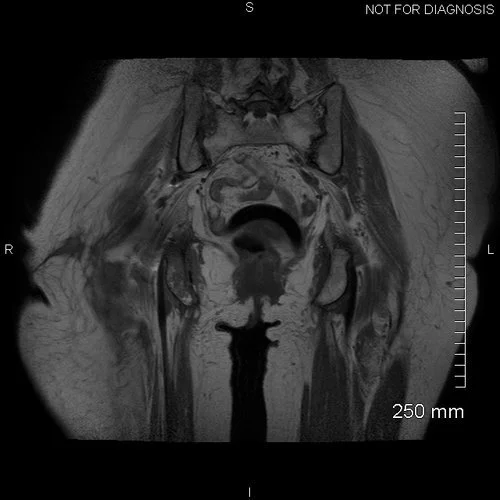

Pre-op MRI demonstrates atrophy of her abductors however there was a tendon attachment present. It demonstrated pockets of fluid around the greater trochanter and in the subcutaneous tissues.

Pre-op CT scan Considerable osteolysis is noted in the proximal femur.